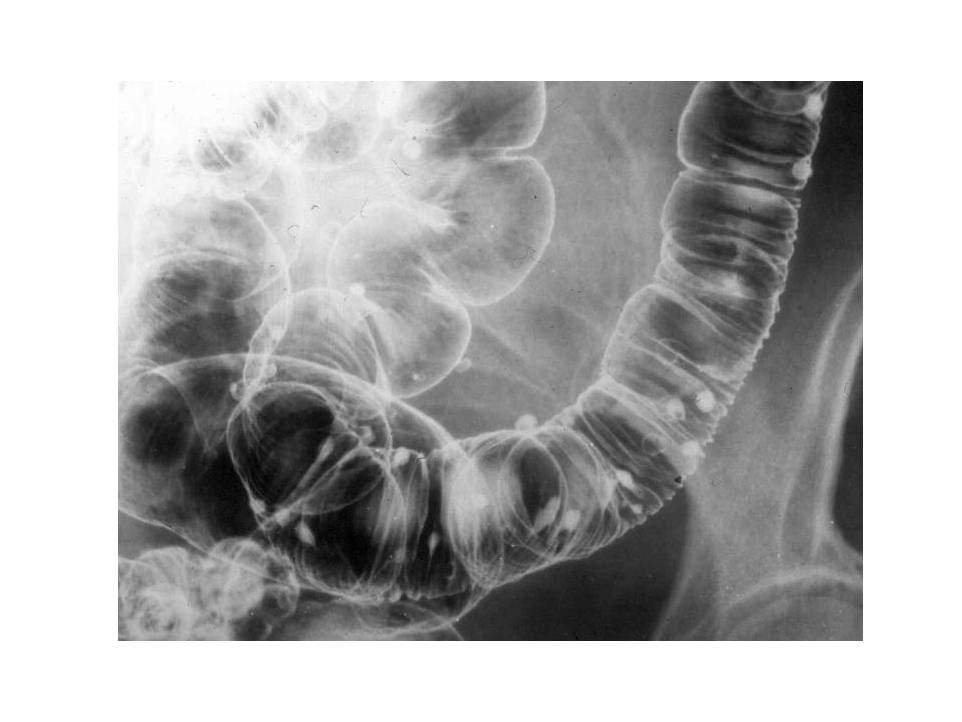

Image

Fig.23.: Radiographic image: multiple, round filling defects are seen on the sigma and on the descending colon.

Fig.24.: Double-contrast irrigoscopy